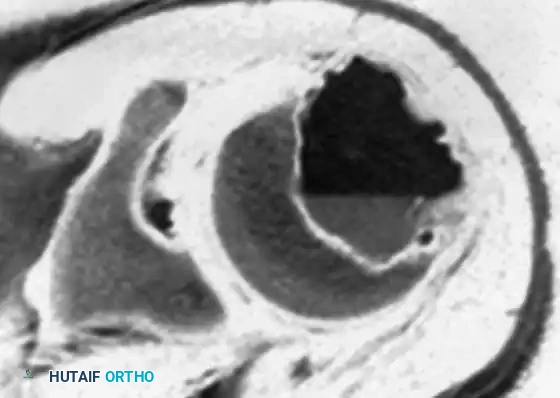

Fig. 21-4C: MRI showing the expansile nature of the lesion.

Fig. 21-4D: MRI demonstrating a distinct fluid-fluid level, indicative of a secondary aneurysmal bone cyst (ABC), which occurs in up to 20% of chondroblastomas.